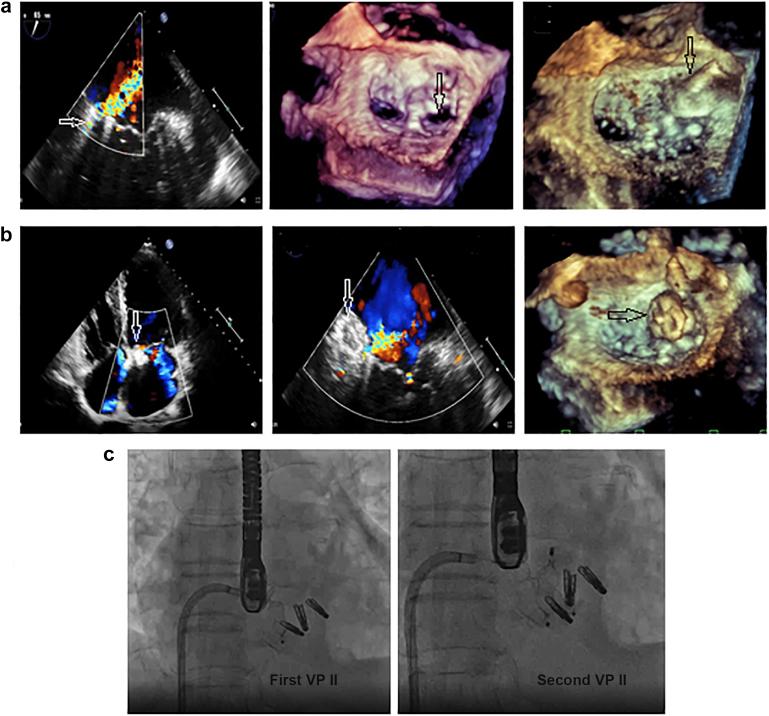

The study enrolled 16 patients; 9 (56.25%) with MVL perforations and 7 (43.75%) with post-MitraClip (Abbott Laboratories, Abbott Park, Illinois) residual MR, with a mean age of 55.75 ± 16.69 years. Mean perforation/jet diameters were 5.75 ± 1.67 and 6.5 ± 1.93 mm, and the mean 3D-vena contracta area was 0.54 ± 0.14 cm. Perforations were crossed retrograde (transaortic in 7 [43.75%] patients and transapical in 2 [12.5%] patients), and post-MitraClip devices residual jets were crossed antegrade (transvenous/transseptal). Six (37.5%) patients required arteriovenous loop formation for device deployment, that was antegrade transvenous/transseptal in 13 (81.25%) patients and retrograde transapical in 3 (18.75%) patients. Devices used were Amplatzer-ASO in 10 (62.5%) patients and Amplatzer-VP-II in 6 (37.5%) patients. Mean procedural and fluoroscopy times were 55.13 ± 16.24 and 16.25 ± 4.03 ​minutes, respectively. Patients passed successfully, without MV gradient change or device-related complications.

本研究共纳入16例患者;9例(56.25%)为MVL穿孔,7例(43.75%)为MitraClip(雅培实验室,伊利诺伊州雅培公园)夹闭术后残留MR,平均年龄为55.75±16.69岁。穿孔/射流平均直径分别为5.75±1.67和6.5±1.93mm,平均三维缩流颈面积为0.54±0.14cm²。穿孔采用逆行穿过(7例[43.75%]经主动脉,2例[12.5%]经心尖),MitraClip装置术后残留射流采用顺行穿过(经静脉/经房间隔)。6例(37.5%)患者需要形成动静脉环以部署装置,其中13例(81.25%)患者采用顺行经静脉/经房间隔,3例(18.75%)患者采用逆行经心尖。使用的装置为10例(62.5%)患者使用Amplatzer-ASO,6例(37.5%)患者使用Amplatzer-VP-II。平均手术时间和透视时间分别为55.13±16.24分钟和16.25±4.03分钟。患者均顺利通过,未出现MV梯度变化或与装置相关的并发症。